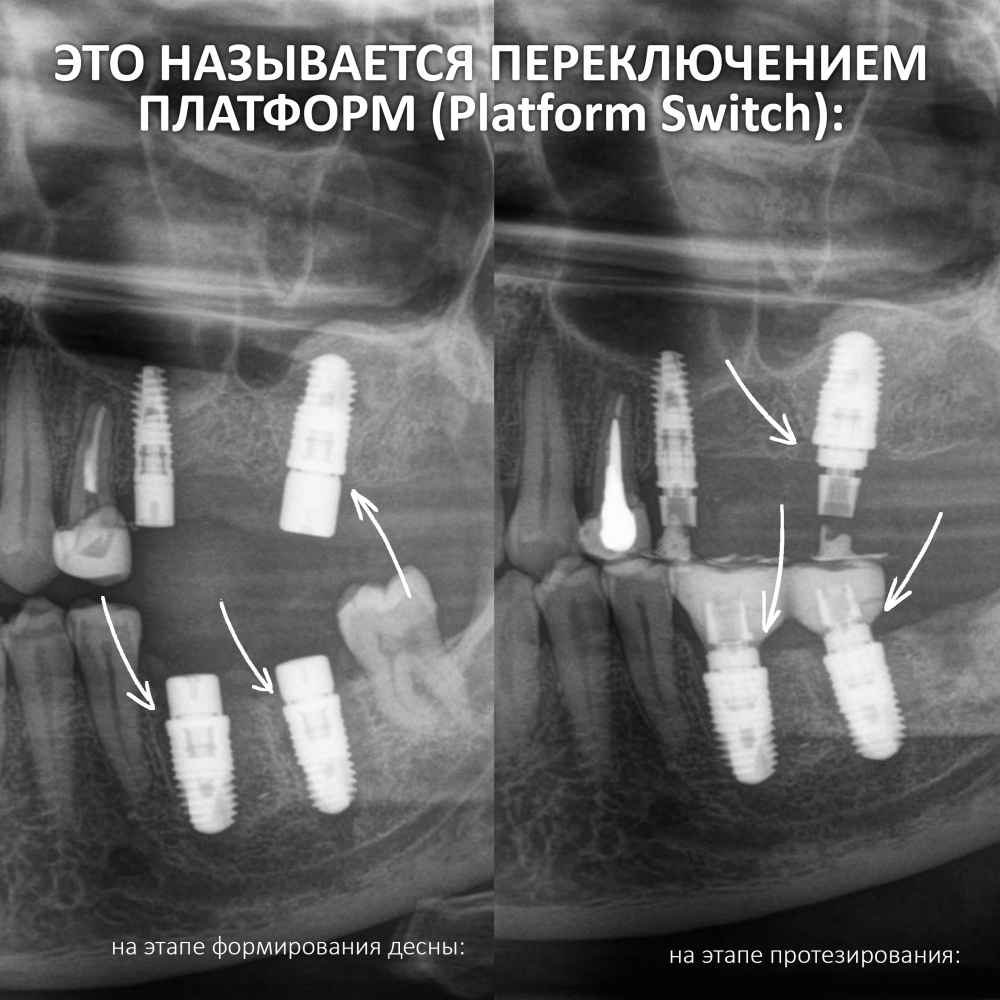

IN Xive WE TRUST (с) — Двенадцать лет работы с Xive